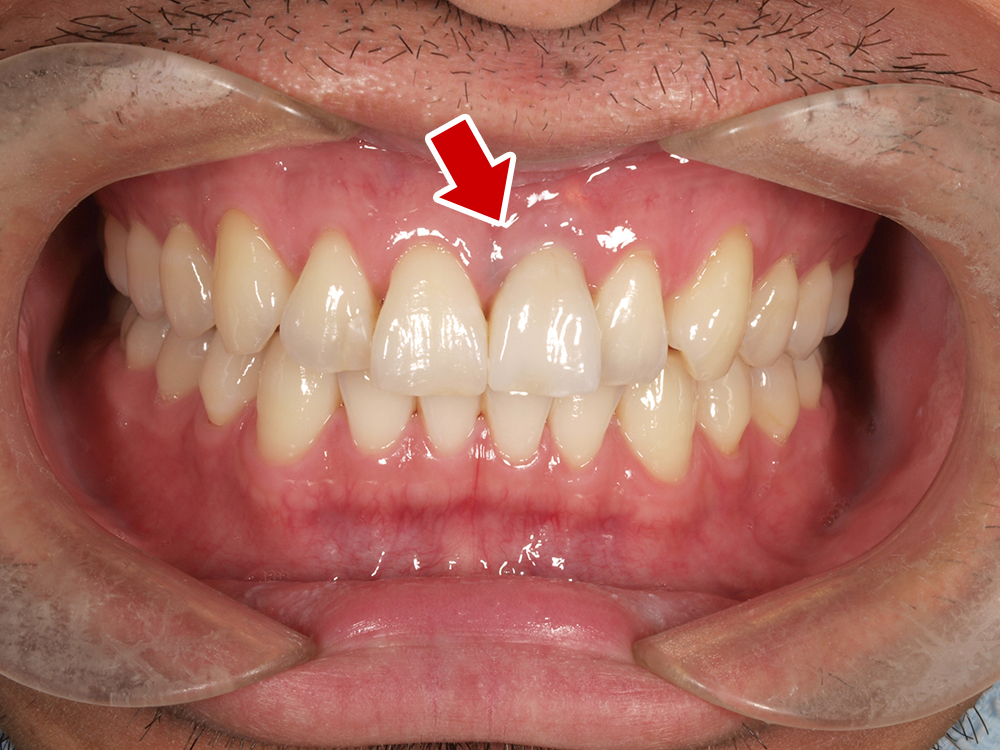

45歳 男性 医療関係者紹介

- 主訴

- 右前歯が取れた(右上2)

- 処置内容

1本インプラント埋入+再生療法

抜歯即時埋入⇒抜歯を行い、同時にインプラント埋入(即時埋入)

- 治療費用

- 上顎:約40万円(税込)

- 治療期間

- 約11か月

- リスク

- 上部構造物、仮歯の破折、術後の腫れ(3日)、人工歯根脱落リスクがあります